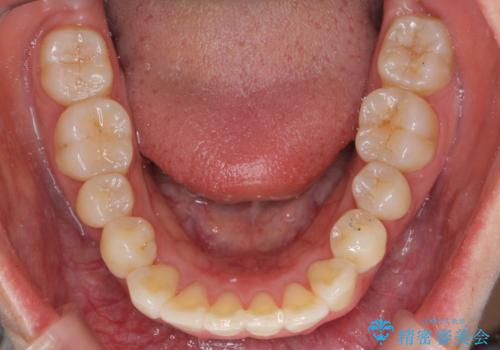

上のワイヤー矯正を半年ほど行い反対咬合を改善してから、上下インビザライン治療を行いました。

下の前歯を中に入れるためにIPR(歯をわずかに削る処置)を行いました。

左上の反対咬合になっていた歯の頬側咬頭は、すでに削れて短くなっていましたがそのまま並べています。